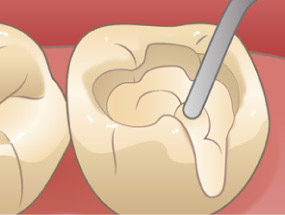

むし歯箇所のみ削り、充填や詰め物で埋めます。

コンポジットレジンは、レジンとフィラーという成分が混合されて出来ています。フィラーとは、シリカ(ガラス)やジルコニア、セラミックなどの粒子のことで、レジンの強度や審美性を高めるために混合されています。よく歯科用プラスチックやレジンと呼ばれます。

歯型を取って、出来上がったものを詰める銀歯などとは違い、コンポジットレジンは歯に直接塗布をするため歯との接着性も良いため、詰め物と歯の間に隙間ができて、詰め物の下に虫歯が発生してしまうという問題はまずありません。